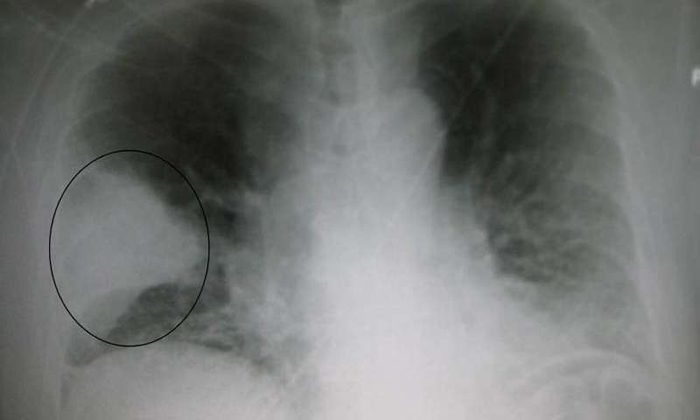

Pneumonia—a severe lung infection—kills up to 24,000 Ugandan children under the age of five per year, many of whom are misdiagnosed as having malaria, according to the UN children’s agency UNICEF.

Traditionally doctors use a stethoscope to listen for abnormal crackling or bubbling sounds in the lungs, however if medics suspect malaria or tuberculosis—which also include respiratory distress—the time lost treating those rather than pneumonia could prove deadly for their patient.